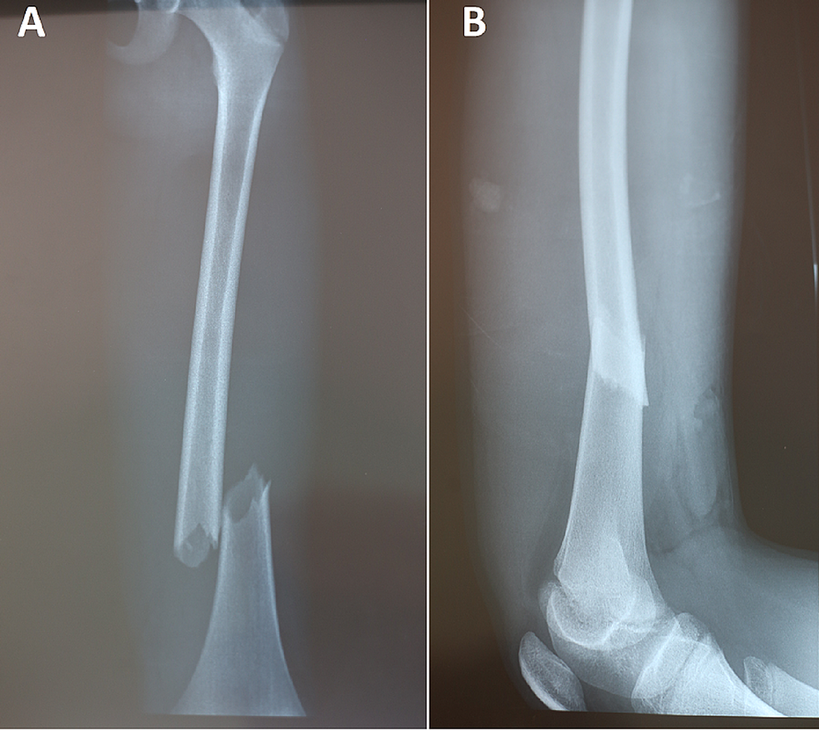

![]() |

| ▲ 골절 capture cureus.com |